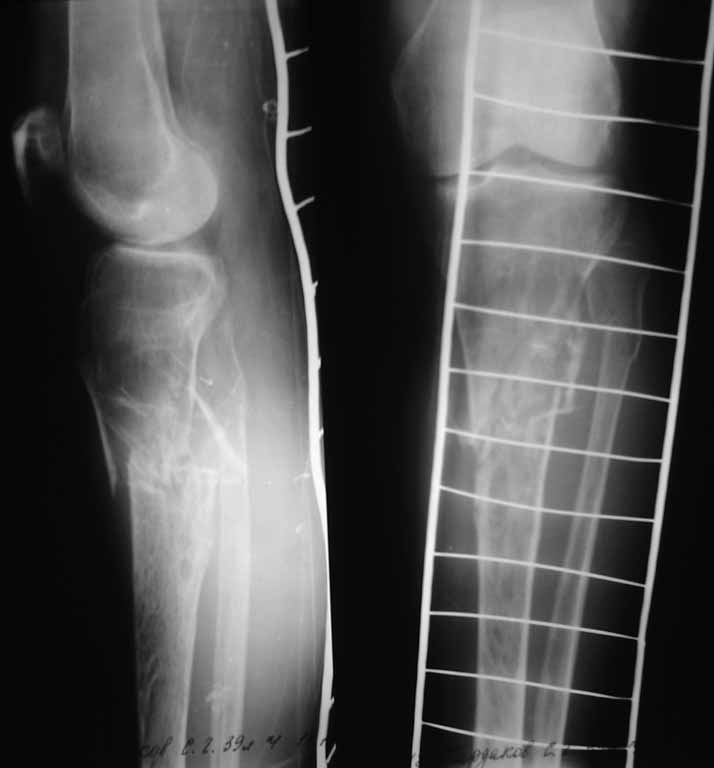

Рентгенологический контроль на скелетном вытяжении прилагается